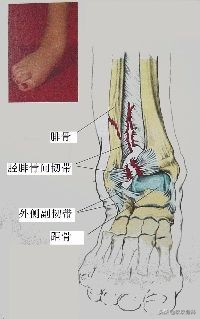

踝关节的韧带损伤▲▲▲

2.踝外侧副韧带损伤

A.单纯韧带损伤

- 踝外侧副韧带的牵扯及部分断裂特点:没有明显关节不稳

- 踝外侧副韧带完全断裂特点:有明显关节不稳

- 常有一时性脱位或半脱位多合并关节囊的撕裂

症状

- 受伤史—内翻伤,旋后伤

- 疼痛、肿胀

- 皮下淤血

- 跛行

- 活动受限

体征

- 肿胀,压痛(注意压痛最明显的部位!)

- 被动内翻后旋后时疼痛明显加重

- 注意检查踝关节有无不稳(抽屉试验、内翻应力试验、距骨侧方移动试验)